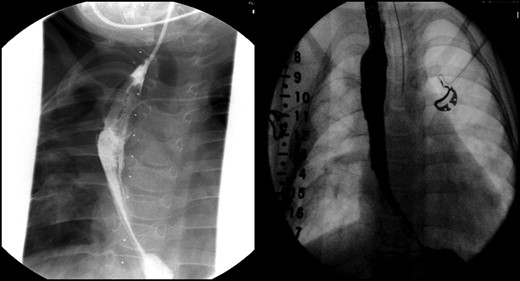

With the distal colon graft in place, as well as the distal esophageal segment, we recommended a combined procedure with graft removal and growth induction given the 8.2-cm gap (Fig. 1A and B). A thoracoabdominal incision was made and the colonic conduit was dissected away from the diaphragm; extensively mobilized from the left lateral segment of the liver and lung; and, transected from its anastomosis with the stomach. The stomach was then repaired in two layers. Traction sutures, using 4.0 prolene sutures, were then placed in the muscular layer of the distal esophageal segment and brought out onto the chest wall.

(A) Lateral view during her initial fluoroscopic examination illustrating a small, distal (lower) esophageal remnant present in situ (Black arrows). Contrast was injected through her existing gastrostomy tube. (B) Anterior–posterior (AP) view during initial fluoroscopic examination illustrating an aperistaltic, native colonic interposition in situ with significant dilatation.